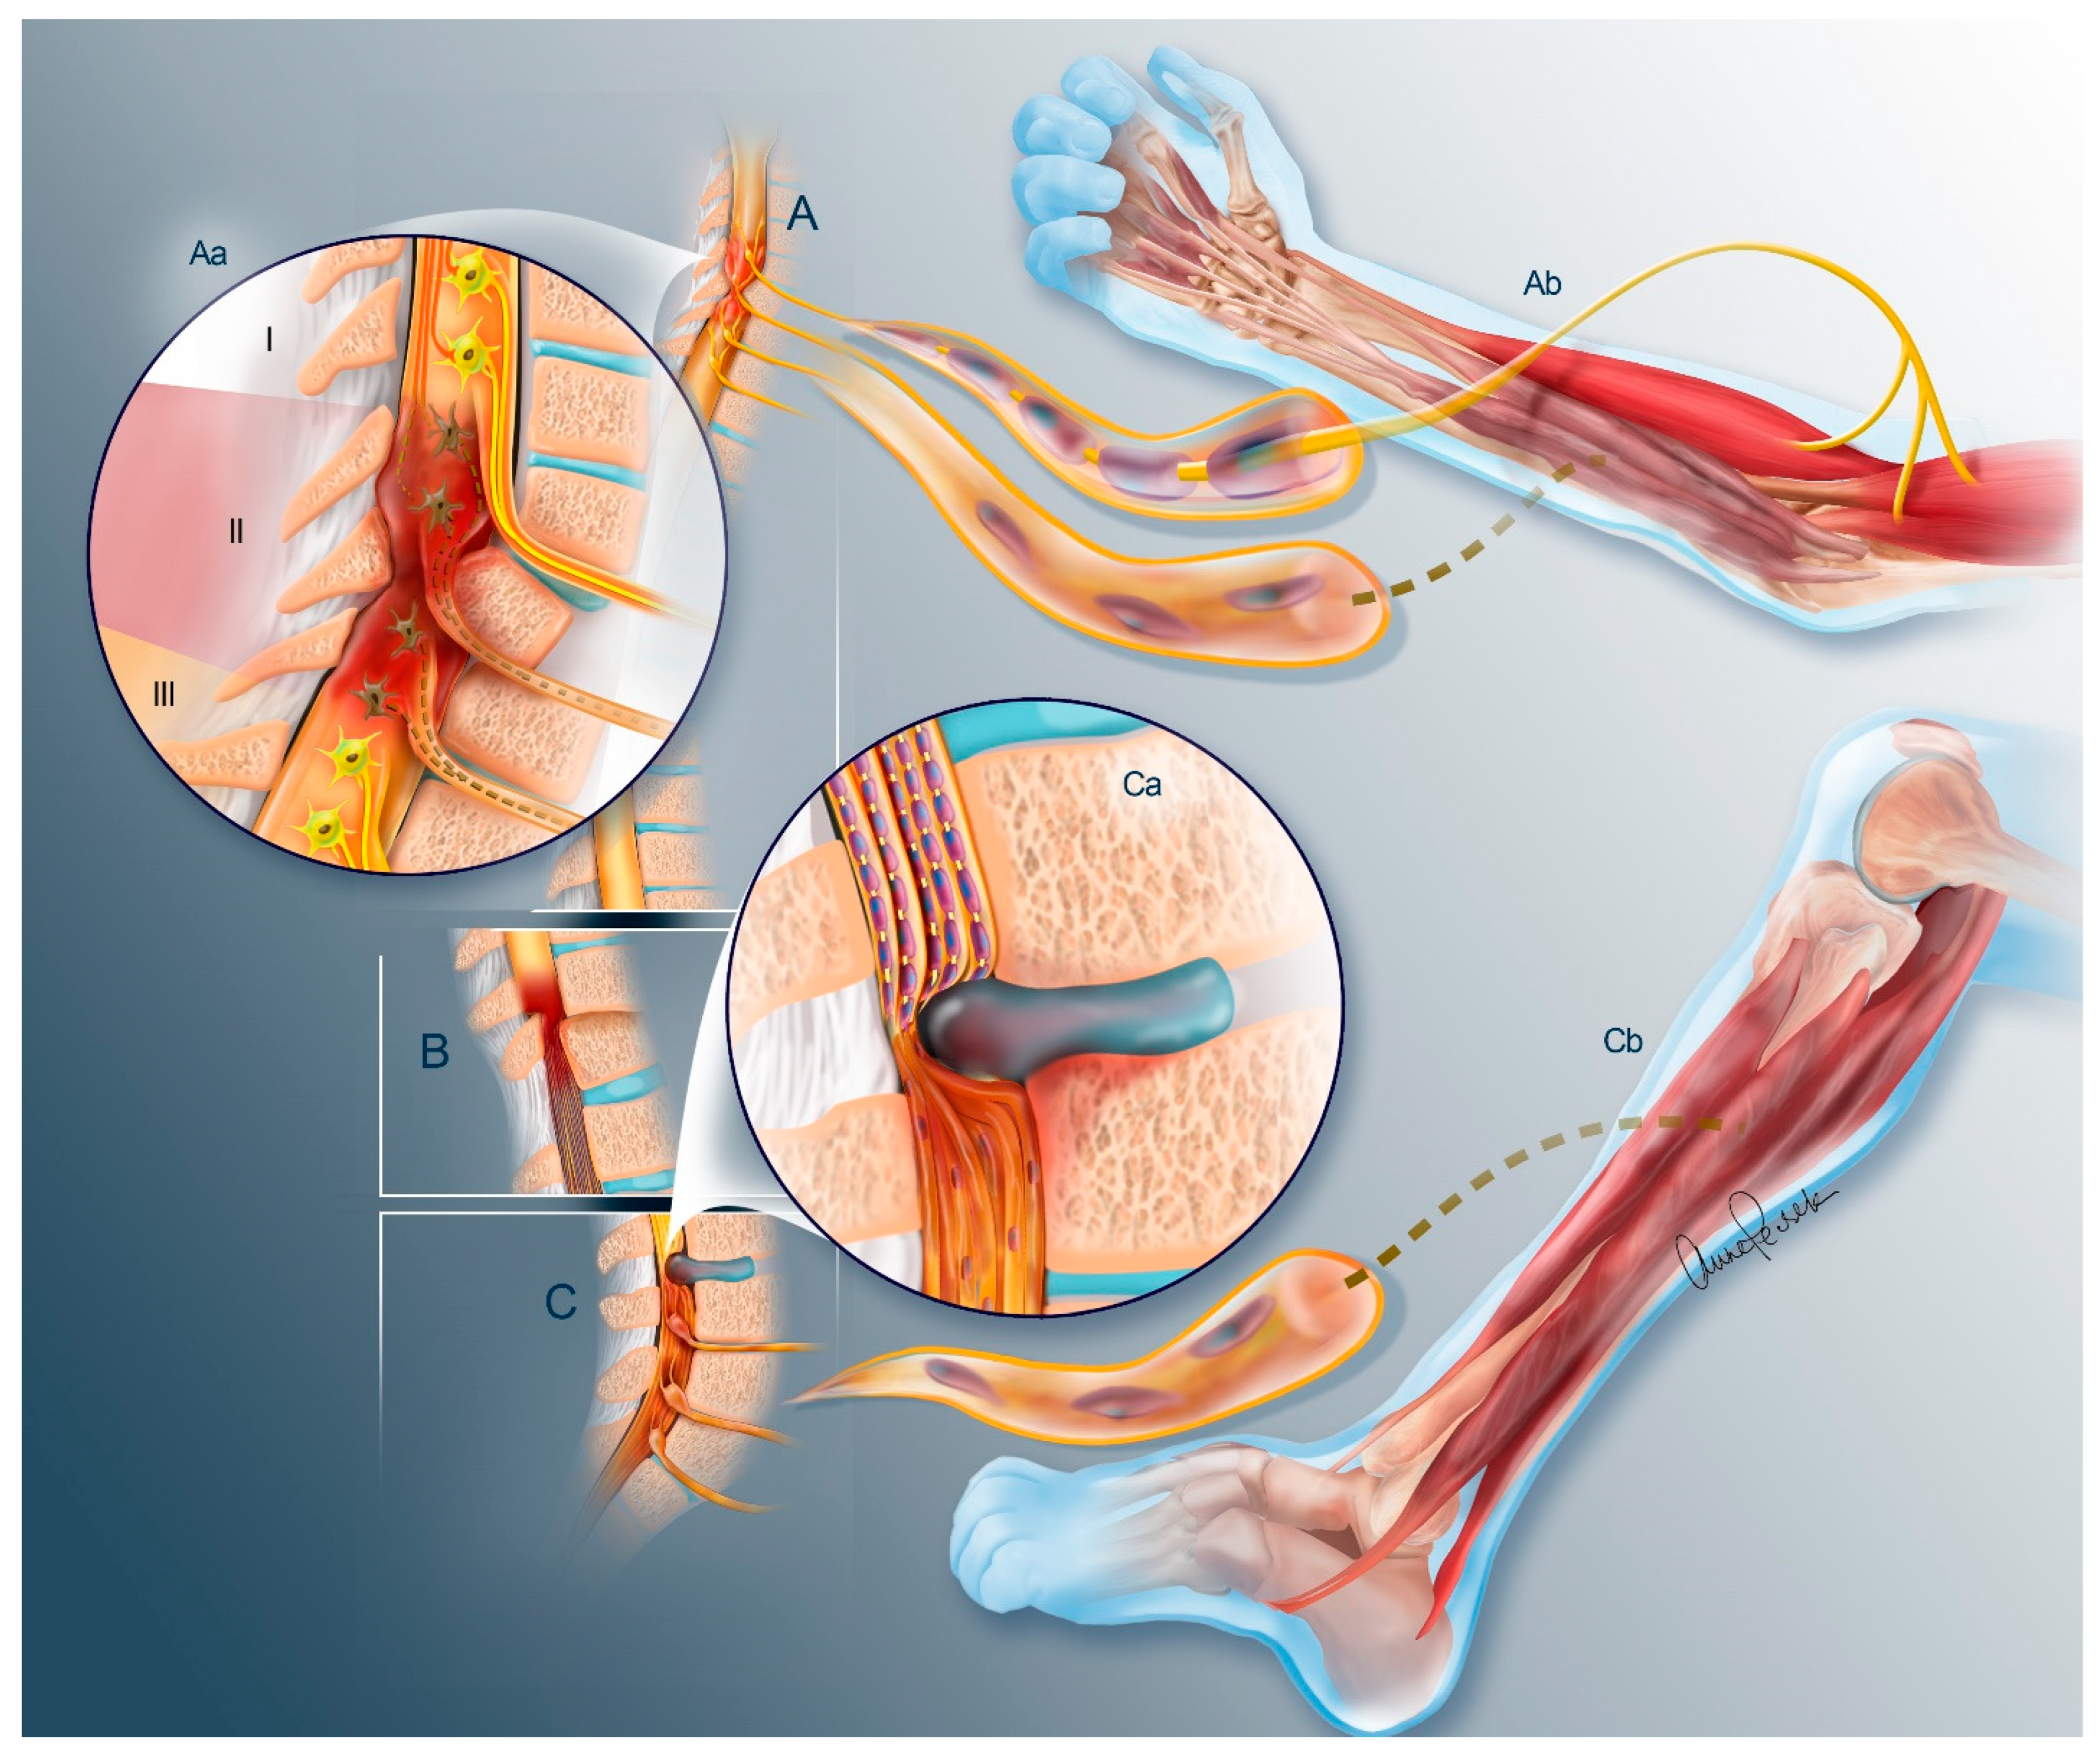

2. The Problem of Denervation Atrophy

2.1. Nerve Trunk

2.2. Neuromuscular Junction

3.1. Nerve Transfers

Sensory Preservation